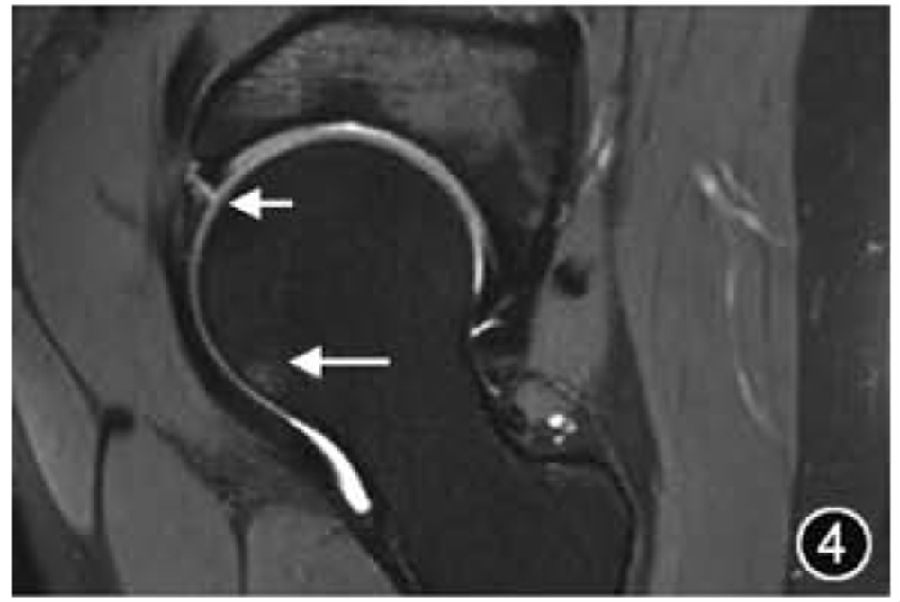

3.FAI:FAI是由股骨近端与髋臼边缘接触碰撞引起,会导致髋臼、盂唇和软骨病变,产生疼痛和功能障碍,并可导致早发性OA。FAI的发病机制可能是由于髋臼较深导致过度覆盖(Pincer型,又称钳夹型)和/或股骨头颈交界处凹陷不足(Cam型,又称凸轮型)导致,两种解剖异常多同时出现(混合型)。FAI的影像学管理和评估应首先进行前后位骨盆X线平片检查,有症状患者应进行蛙式位检查及CT检查,以全面评估髋臼及股骨头颈部形态。MRI也是全面评估FAI的重要手段,主要侧重于评估盂唇、软骨的损伤程度及范围,前盂唇是FAI的主要损伤部位(图4)。需要注意的是,只有当典型的影像学特征与临床症状同时出现时,才能做出FAI的诊断。

图4 髋关节撞击MRI图像。冠状面T2WI示髋臼外上盂唇撕裂(短↑)伴有股骨头颈交界处骨髓水肿(长↑)